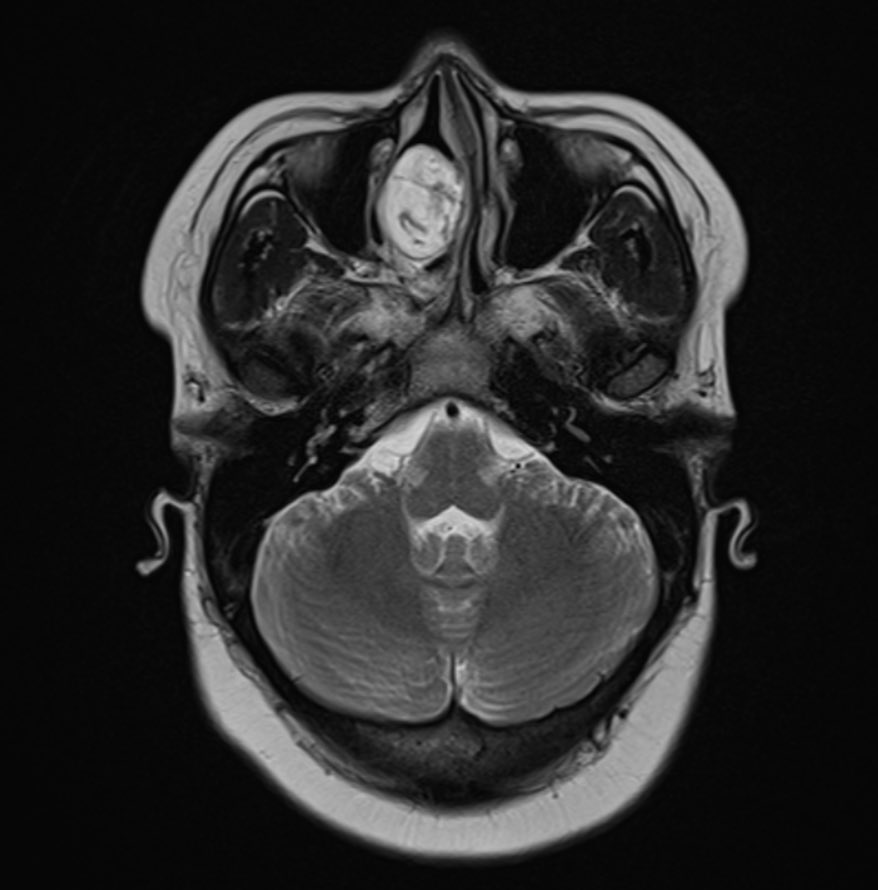

🔍 Case of the Day | The Value of MRI in Recurrent Meningitis A 29-year-old female presents with recurrent episodes of meningitis, without prior trauma or surgery. Clinical suspicion: occult anterior skull base defect. 🩻 MRI Brain: • Cribriform plate defect measuring 9.8 ×…